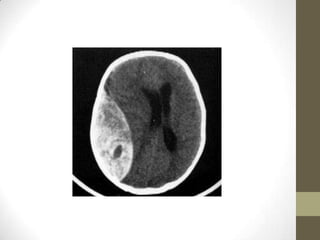

• O espaço extradural ou epidural normalmente não é um

do crânio e a camada periosteal externa da dura-máter. Tornase um espaço real apenas patologicamente, por exemplo, no

hematoma extradural.

Hematoma Extradural

• O espaçoextradural ou epidural normalmente não é um espaço real mas apenas um espaço potencial entre os ossos do crânio e a camada periosteal externa da dura-máter. Tornase um espaço real apenas patologicamente, por exemplo, no hematoma extradural.